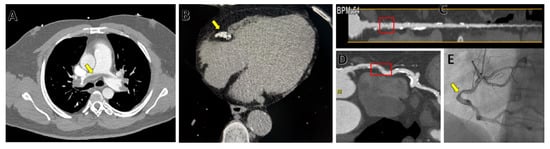

5. Computed Tomography (CT)

- Shirani, F.; Shayganfar, A.; Hajiahmadi, S. COVID-19 pneumonia: A pictorial review of CT findings and differential diagnosis. Egypt. J. Radiol. Nucl. Med. 2021, 52, 38. [Google Scholar] [CrossRef]

- Cereda, A.; Toselli, M.; Palmisano, A.; Vignale, D.; Khokhar, A.; Campo, G.; Bertini, M.; Loffi, M.; Andreini, D.; Pontone, G.; et al. Coronary calcium score as a predictor of outcomes in the hypertensive Covid-19 population: Results from the Italian (S) Core-Covid-19 Registry. Hypertens. Res. 2021, 45, 333–343. [Google Scholar] [CrossRef]

| Phase | Details |

|---|---|

| Preparation | Administer B-blockers until heart rate is <70 bpm (not appliable for the newest machines with 256+ slices) |

| Use venous canula of at least 20 G | |

| Coronary Calcium Score | ECG-gated, breathhold |

| Acquisition from tracheal carina until 2 cm under cardiac shadow on survey scans | |

| Calcium score calculation using dedicated software | |

| CT Angiography | Injection protocol |

| Use contrast agent with concentration of 300–400 mg of iodine/mL Two phase injection: 1. 80–120 mL of contrast media, 5–6 mL/s 2. 30–40 mL of saline, 5–6 mL/s | |

| ECG-gated, breathhold | |

| Acquisition from just over the aortic arch until 2 cm under the heart | |

| Acquisition window 30–80% Contrast monitor plane on the tracheal carina | |

| Manual breathhold and acquisition start: 1. Breathhold command when pulmonary artery has maximum opacification 2. Start 3 s delay acquisition when aorta starts opacifying |